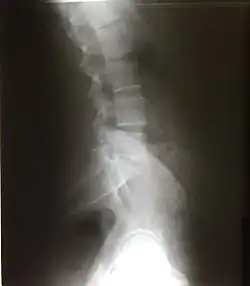

Позвоночник человека состоит из 32—33 позвонков, последовательно соединённых друг с другом в вертикальном положении. Позвоночный столб выполняет функцию опоры, защиты спинного мозга и участвует в движениях туловища и головы[16]. Независимо от принадлежности к какому-либо отделу позвоночного столба, все позвонки, за исключением первого и второго шейных, имеют общий план строения. В позвонке различают тело и дугу. Тело позвонка (лат. corpus vertebrae) обращено вперёд и выполняет опорную функцию. Дуга позвонка (лат. arcus vertebrae) соединяется сзади с телом с помощью ножек дуг позвонка (лат. pediculli arcus vertebrae). Между телом и дугой располагается позвоночное отверстие (лат. foramen vertebrale). В совокупности все позвоночные отверстия образуют позвоночный канал (лат. canalis vertebralis), где находится спинной мозг. От дуги позвонка отходят отростки: сзади в сагиттальной плоскости остистый отросток (лат. processus spinalis), направо и налево от дуги — поперечные отростки (лат. processus transversus), вверх и вниз от дуги — верхние и нижний суставные отростки (лат. processus articulares superiores et inferiores). Основания суставных отростков ограничены верхними и нижними позвоночными вырезками (лат. incisurae vertebrales superiores et inferiores), которые при соединении соседних позвонков образуют межпозвоночные отверстия (лат. foramina intervertebralia). Через эти отверстия проходят кровеносные сосуды и спинномозговые нервы.

Различают 5 отделов позвоночника:

- Шейный отдел (7 позвонков, C1—C7);

- Грудной отдел (12 позвонков, Th1—Th12);

- Поясничный отдел (5 позвонков, L1—L5);

- Крестцовый отдел (5 позвонков, сросшихся в одну крестцовую кость или крестец);

- Копчиковый отдел (3-4 позвонков).

Есть 2 вида изгиба позвоночника: лордоз и кифоз. Лордоз — это те части позвоночника, которые выгнуты вентрально (вперед) — шейный и поясничный. Кифоз — это те части позвоночника, которые выгнуты дорсально (назад) — грудной и крестцовый.